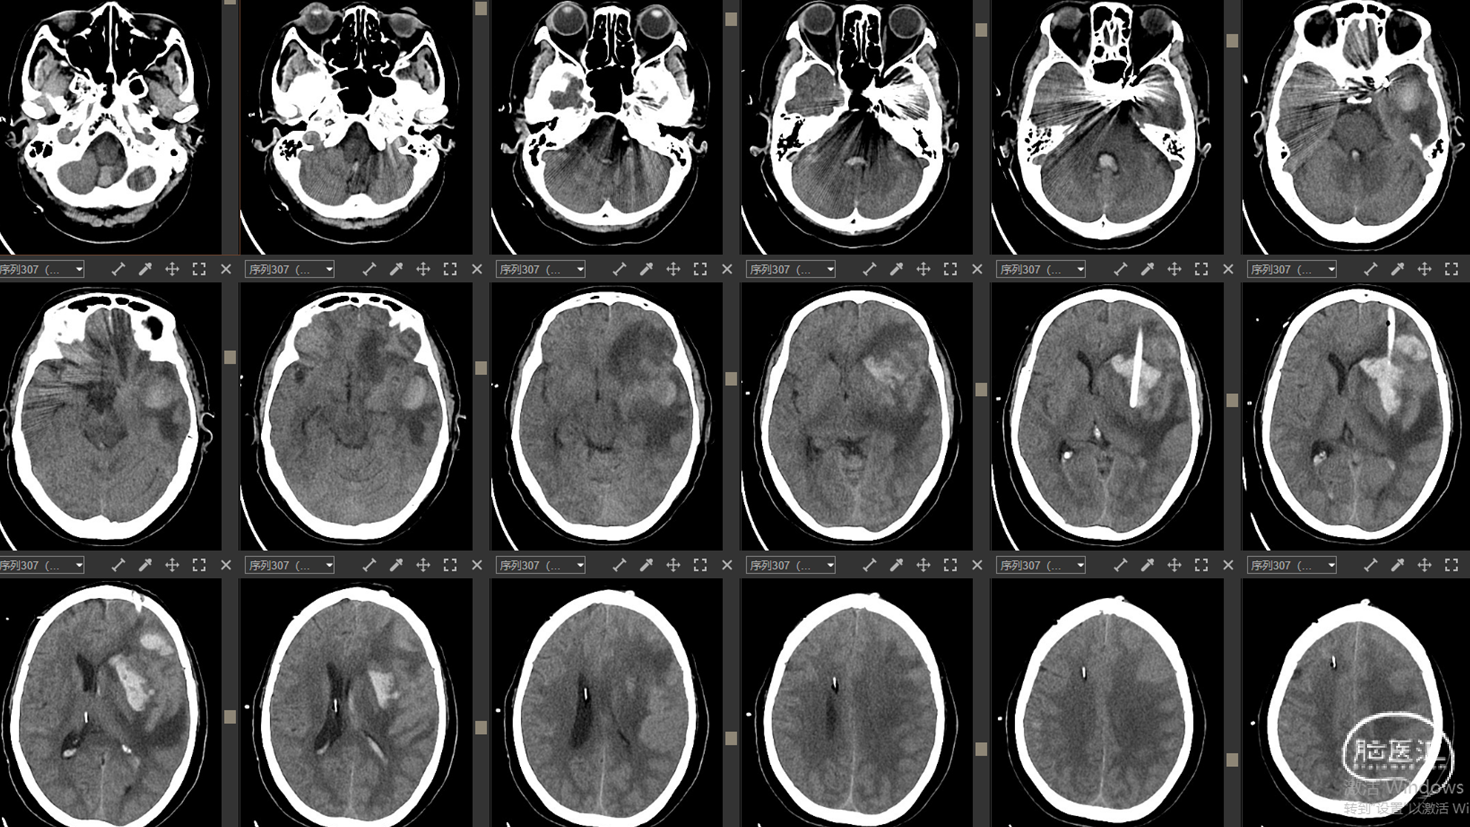

影像资料:CT、CTA

1. 左侧基底节区及左侧额颞叶血肿

2. 左侧颈内C4段动脉瘤破裂致颈内动脉海绵窦瘘(Barrow A型)

精确诊断:左侧颈内C4段动脉瘤破裂至大脑中浅静脉致左侧基底节区及左侧额颞叶静脉性梗死并出血转化。

· 一期:左侧颈内动脉C4段动脉瘤弹簧圈栓塞术(双微导管技术)

· 二期:左侧基底节区血肿穿刺引流术(备开颅血肿清除术+去骨瓣减压术)

术后检查